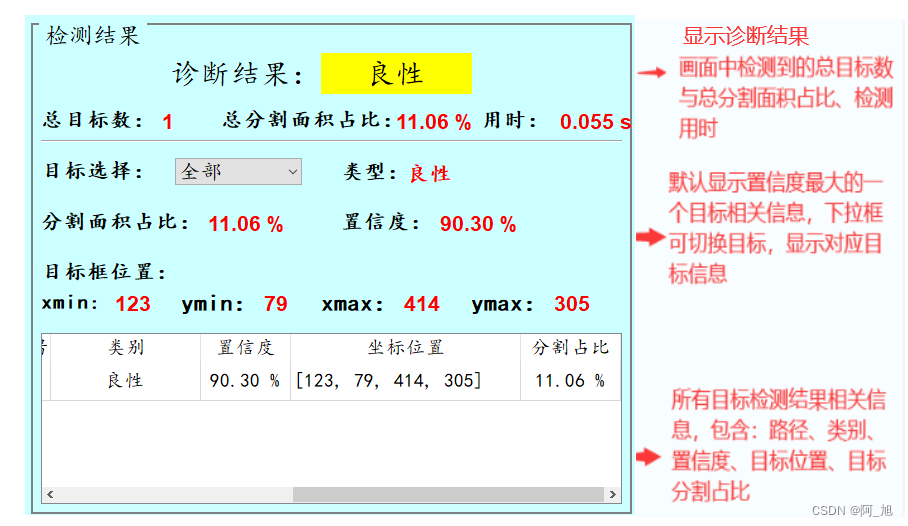

检测结果界面如下:

检测结果说明:

诊断结果区域:分别用'绿色'、‘黄色’、‘红色’背景代表‘正常’、‘良性’、‘恶性’这3种类别的检测结果。

显示效果如下:

1. 可进行乳腺癌肿瘤的检测与分割,并判断肿瘤类型:['良性', '恶性'],在诊断结果区域显示['正常'、'良性', '恶性']这3种诊断结果;

3. 可显示总分割面积占比以及单个目标的分割面积占比;

4. 界面可实时显示目标位置、分割结果、分割面积占比、置信度、用时等信息;

5. 结果保存:支持图片、视频及摄像头的分割结果保存;

界面参数设置说明

置信度阈值:也就是目标检测时的conf参数,只有检测出的目标置信度大于该值,结果才会显示;交并比阈值:也就是目标检测时的iou参数,只有目标检测框的交并比大于该值,结果才会显示;窗口1:显示分割结果:表示是否在检测图片中显示分割结果,默认勾选;窗口1:显示检测框与标签:表示是否在检测图片中显示检测框与标签,默认勾选;窗口2:显示Mask或者显示原始分割图片:表示在窗口2中显示分割的Mask或者原始图片分割内容;

2.点击目标下拉框后,可以选定指定目标的结果信息进行显示。

4.点击表格中的指定行,界面会显示该行表格所写的信息内容。

注:右侧目标位置默认显示置信度最大一个目标位置,可用下拉框进行信息切换。所有检测结果均在表格中显示。